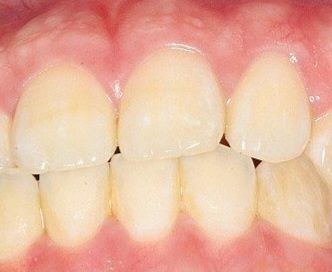

윗니가 아랫니 포개기는 하는데 겨우포개는 느낌이듭니다 윗니가 앞으로 나온게 적은건지 아랫니가 많이 나온걸까요?

이정도만 포개도 상관없는축에 속하나요?

이정도면 정상범주에 속합니다. 윗니가 아랫니 보다 통성 2-3mm 정도 앞으로 나옵니다.

사진상으로 보았을 때는 치축의 각도가 정상 범주에서 벗어나는 것이 맞습니다. 다만 치열이 고르고 특별히 불편감이 없다면 치료의 대상은 아닙니다. 오히려 현재 골격에서 아래 위 치아의 치열 각도를 바꾸게 되면 심미적으로 더 이상해보일 수 있으므로 정확한 교정적 평가 이후에 교정을 하는 것이 필요하며 교정 이후에 오히려 어색해보일 수도 있어 보입니다.

윗니가 아랫니를 수직적으로 2-3mm덮는게 정상입니다.

사진상으로 큰 문제는 없어보입니다.

이상적인 피개교합은 2mm입니다.

사진상으로는 크게 이상은 없어 보입니다. 윗니가 아랫니를 덮는정도면 몇mm이며, 너무 깊게 물리거나 끝이 물리는게 더 안좋은 상태입니다. 크게 걱정은 안하셔도될것같습니다.